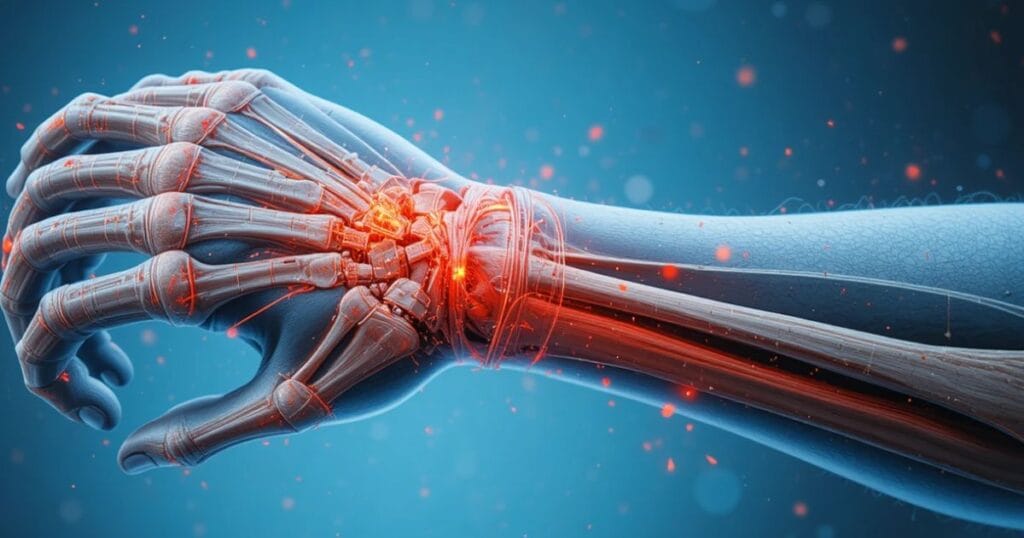

The wrist is a complex structure of bones, ligaments, tendons and nerves. When it suffers damage in an “auto accident wrist damage” event, even seemingly minor injuries—like a sprain—can lead to long-term consequences without proper treatment. Because of that connection, early recognition and action matter immensely.

When you sustain a motor vehicle accident injury to the wrist, the intricate anatomy makes the region vulnerable. Bones such as the radius and ulna, small carpal bones, tendons and the median nerve are all at risk. The result: hand and wrist trauma that affects grip strength, flexibility, even your job.

In cases where the wrist absorbs sudden hyper-extension or jolt during a crash, you may face injuries worse than you anticipate. Harsh forces can produce a wrist ligament injury from accident or trigger carpal tunnel after car crash because of swelling compressing the median nerve. Understanding that injury potential helps you prepare for both medical and legal steps.